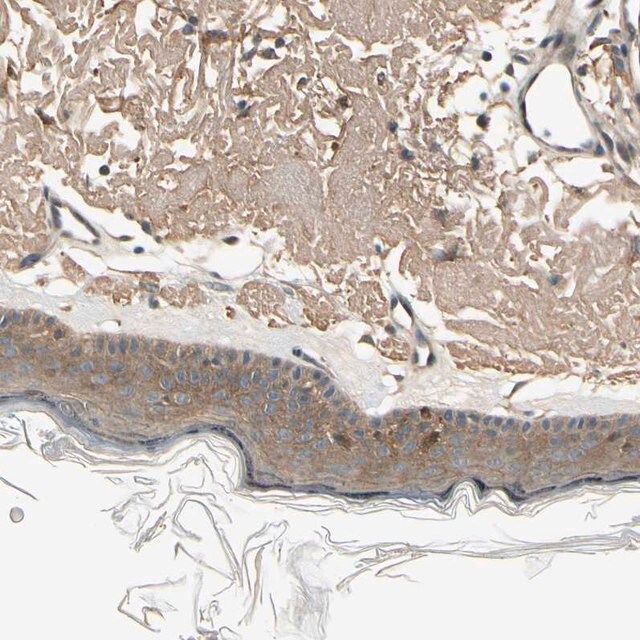

| General description【一般描述】 | Ephrin type-B receptor 3 (EPHB3) belongs to the family of Eph receptor tyrosine kinases. |

| Application【应用】 | All Prestige Antibodies Powered by Atlas Antibodies are developed and validated by the Human Protein Atlas (HPA) project (www.proteinatlas.org)and as a result, are supported by the most extensive characterization in the industry. The Human Protein Atlas project can be subdivided into three efforts: Human Tissue Atlas, Cancer Atlas, and Human Cell Atlas. The antibodies that have been generated in support of the Tissue and Cancer Atlas projects have been tested by immunohistochemistry against hundreds of normal and disease tissues and through the recent efforts of the Human Cell Atlas project, many have been characterized by immunofluorescence to map the human proteome not only at the tissue level but now at the subcellular level. These images and the collection of this vast data set can be viewed on the Human Protein Atlas (HPA) site by clicking on the Image Gallery link. To view these protocols and other useful information about Prestige Antibodies and the HPA, visit sigma.com/prestige. |

| Biochem/physiol Actions【生化/生理作用】 | Ephrin type-B receptor 3 (EPHB3) possesses a catalytic activity and is involved in the regulation of cell adhesion and migration. This catalytic activity is needed for inhibition of integrin-mediated cell adhesion. EPHB3 is distinctively involved in a signaling pathway of Rho GTPases where specific receptors mediate the prevention of directional cell migration. |

| technique(s) | immunoblotting: 0.04-0.4 μg/mL immunohistochemistry: 1:20-1:50 |